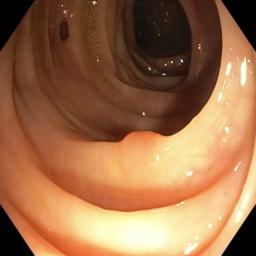

Table I presents our extensive experiments on the polyp segmentation results under FedAvg and FedProx frameworks and benchmarking results with other algorithms. For the metrics defined above, we have highlighted the best-obtained results in bold. Fig. 4 shows samples of the polyp segmentation results. Our comprehensive evaluations reveal that thresholding-based FDG methods (either soft or hard-thresholding) perform better than others.